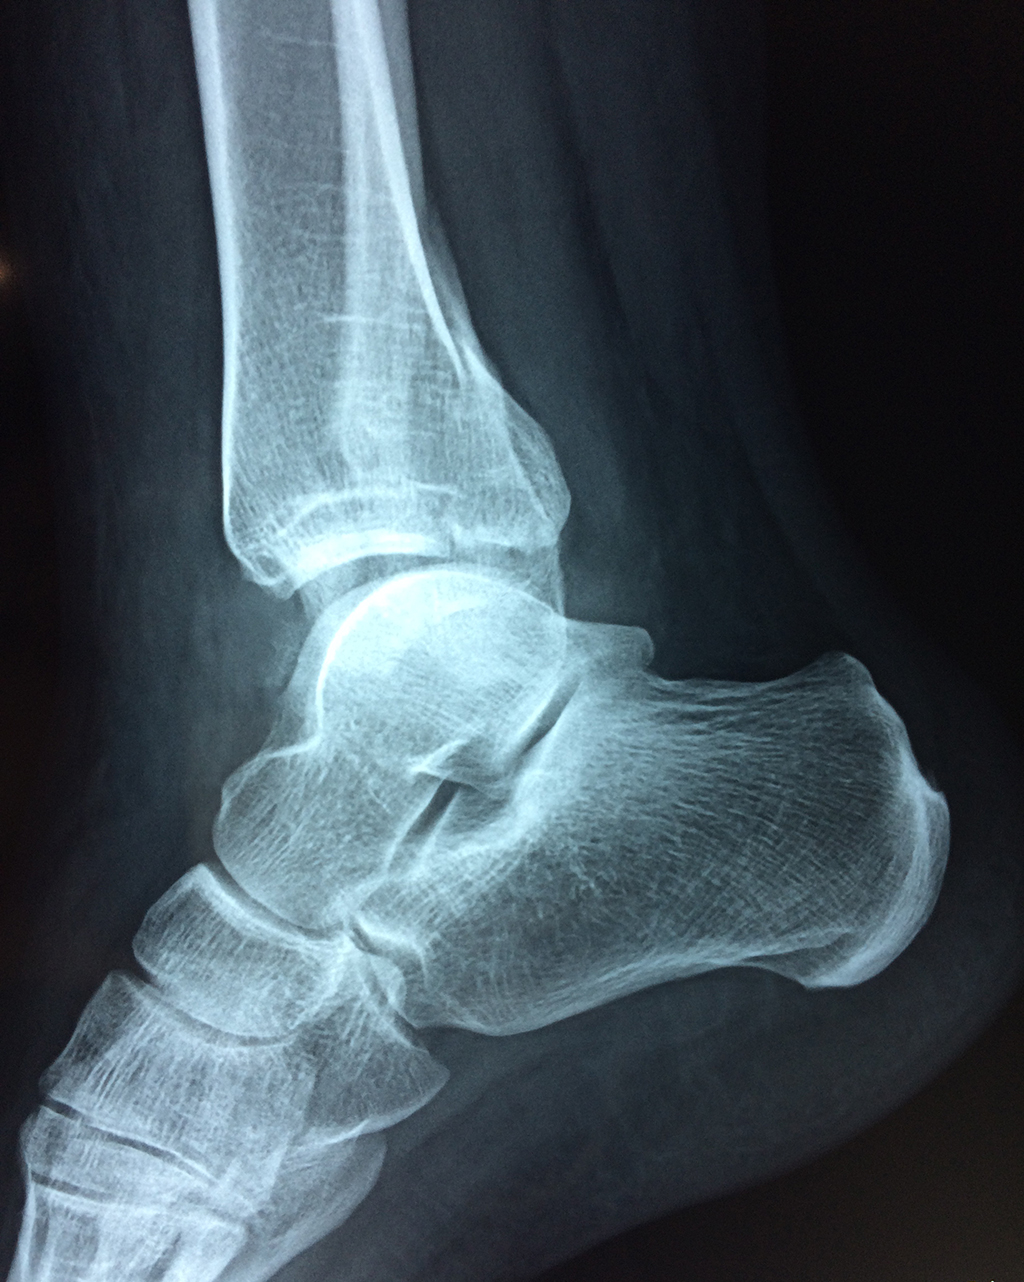

Una fractura de tobillo es la rotura de uno o más de los huesos del tobillo. Estas fracturas pueden ser:

• Parciales (el hueso está sólo parcialmente fisurado, no del todo).

• Completas (el hueso está perforado y está en 2 partes).

• Producirse en uno o ambos lados del tobillo.

Algunas fracturas de tobillo pueden requerir cirugía si:

• Los extremos de los huesos están desalineados entre sí (desplazados).

• La fractura se extiende hasta la articulación del tobillo (fractura intra-articular).

• Los tendones o ligamentos (tejidos que sujetan los músculos y los huesos entre sí) están rotos.

• El médico cree que sus huesos probablemente no sanen apropiadamente sin cirugía.

• El médico considera que la cirugía puede permitirle una recuperación más rápida y confiable.

• En los niños, la fractura involucra la parte del hueso del tobillo donde el hueso está creciendo.

Cuando se necesita cirugía, es probable que esta implique el uso de clavijas de metal, tornillos o placas para sostener los huesos en su lugar mientras la fractura se consolida. Los elementos de soporte pueden ser temporales o permanentes.